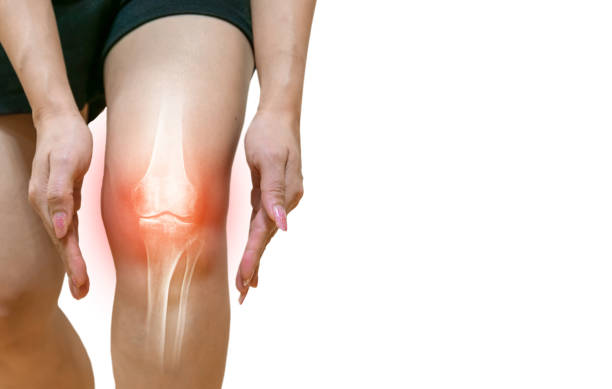

무릎 관절염에 의한 무릎 통증

무릎 관절염은 무릎 관절의 연골과 주변 조직들이 염증을 일으키는 질환으로, 노화, 과부하, 외상 등이 원인이 됩니다. 무릎 관절이 불안정해지고 염증이 발생하면 통증, 부종, 관절 강직 등의 증상이 나타납니다. 운동, 체중 감량, 약물 치료 등이 치료 방법으로 사용됩니다. 특히 중증도가 높은 경우 수술 치료가 필요할 수 있습니다.